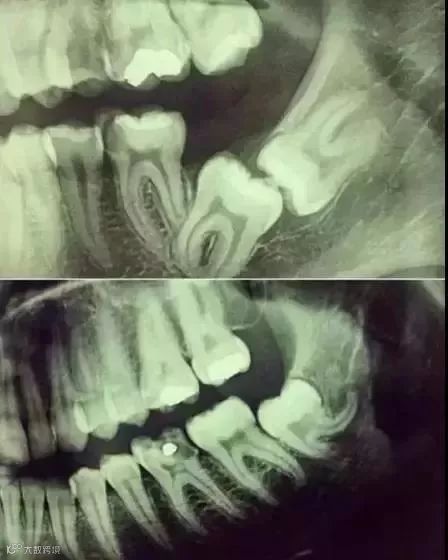

▼

下面这个是接近牙髓了:

牙齿的牙根是埋在牙槽骨中的

医生没有透视眼

为了解患牙的牙根的形态、走向

长度及根尖周有无病变及病变大小

或者怀疑有肉眼无法确认的其它牙科问题

都会建议患者去牙科的X光

甚至,口腔CT来全面性地确认问题

以制定合适的治疗计划